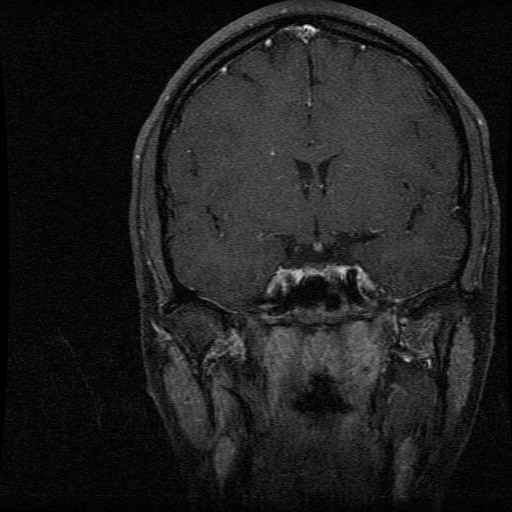

Schedel